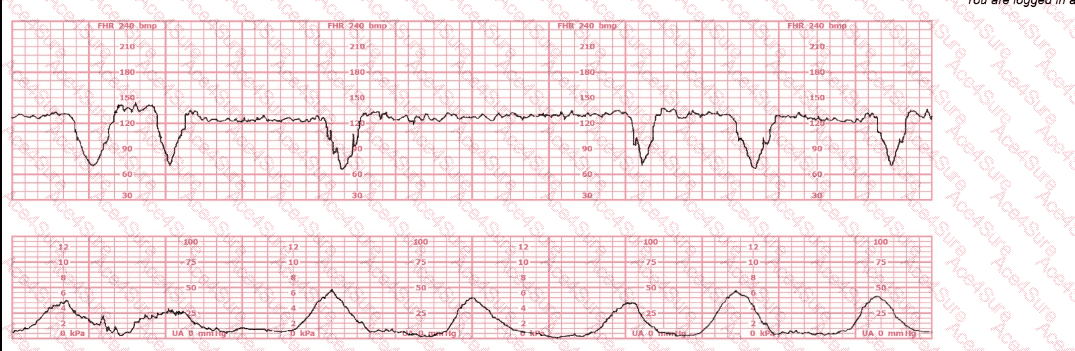

The tracing clearly shows recurrent deep variable decelerations, characterized by:

Abrupt onset (<30 sec)

Sharp V-shape

Rapid descent and ascent

Depth exceeding 60–70 bpm drops

Occurring with most contractions

This pattern is highly consistent with cord compression, which is the physiologic basis of variable decelerations. According to NCC, NICHD, AWHONN, Miller, and Menihan, recurrent (≥50% of contractions) deep variables with slow return to baseline indicate fetal compromise and require targeted intervention.